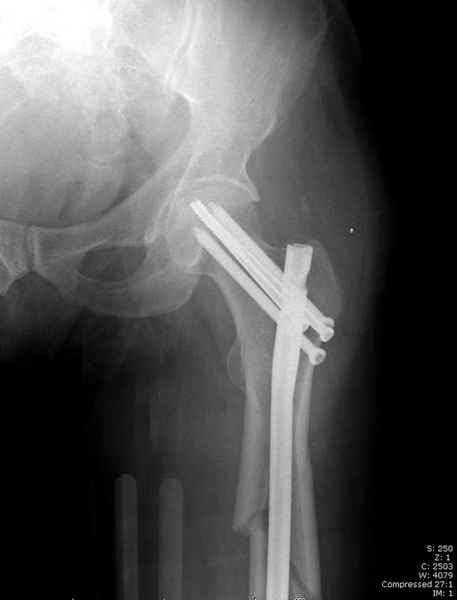

Учитывая, что случай ургентный, больной поступил вечером, не стали делать вытяжение и срочно провели операцию по фиксации перелома бедра антеградным штифтом Versa Nail от DePuy.

Для профилактики дальнейшего раскола в шейке предварительно во время проксимального рассверливания спереди и сзади провели временные спицы, которые в дальнейшем были заменены на шурупы (miss nail method)

Кровотечение удалось контролировать, и больной через пару дней выписан на амбулаторное лечение.